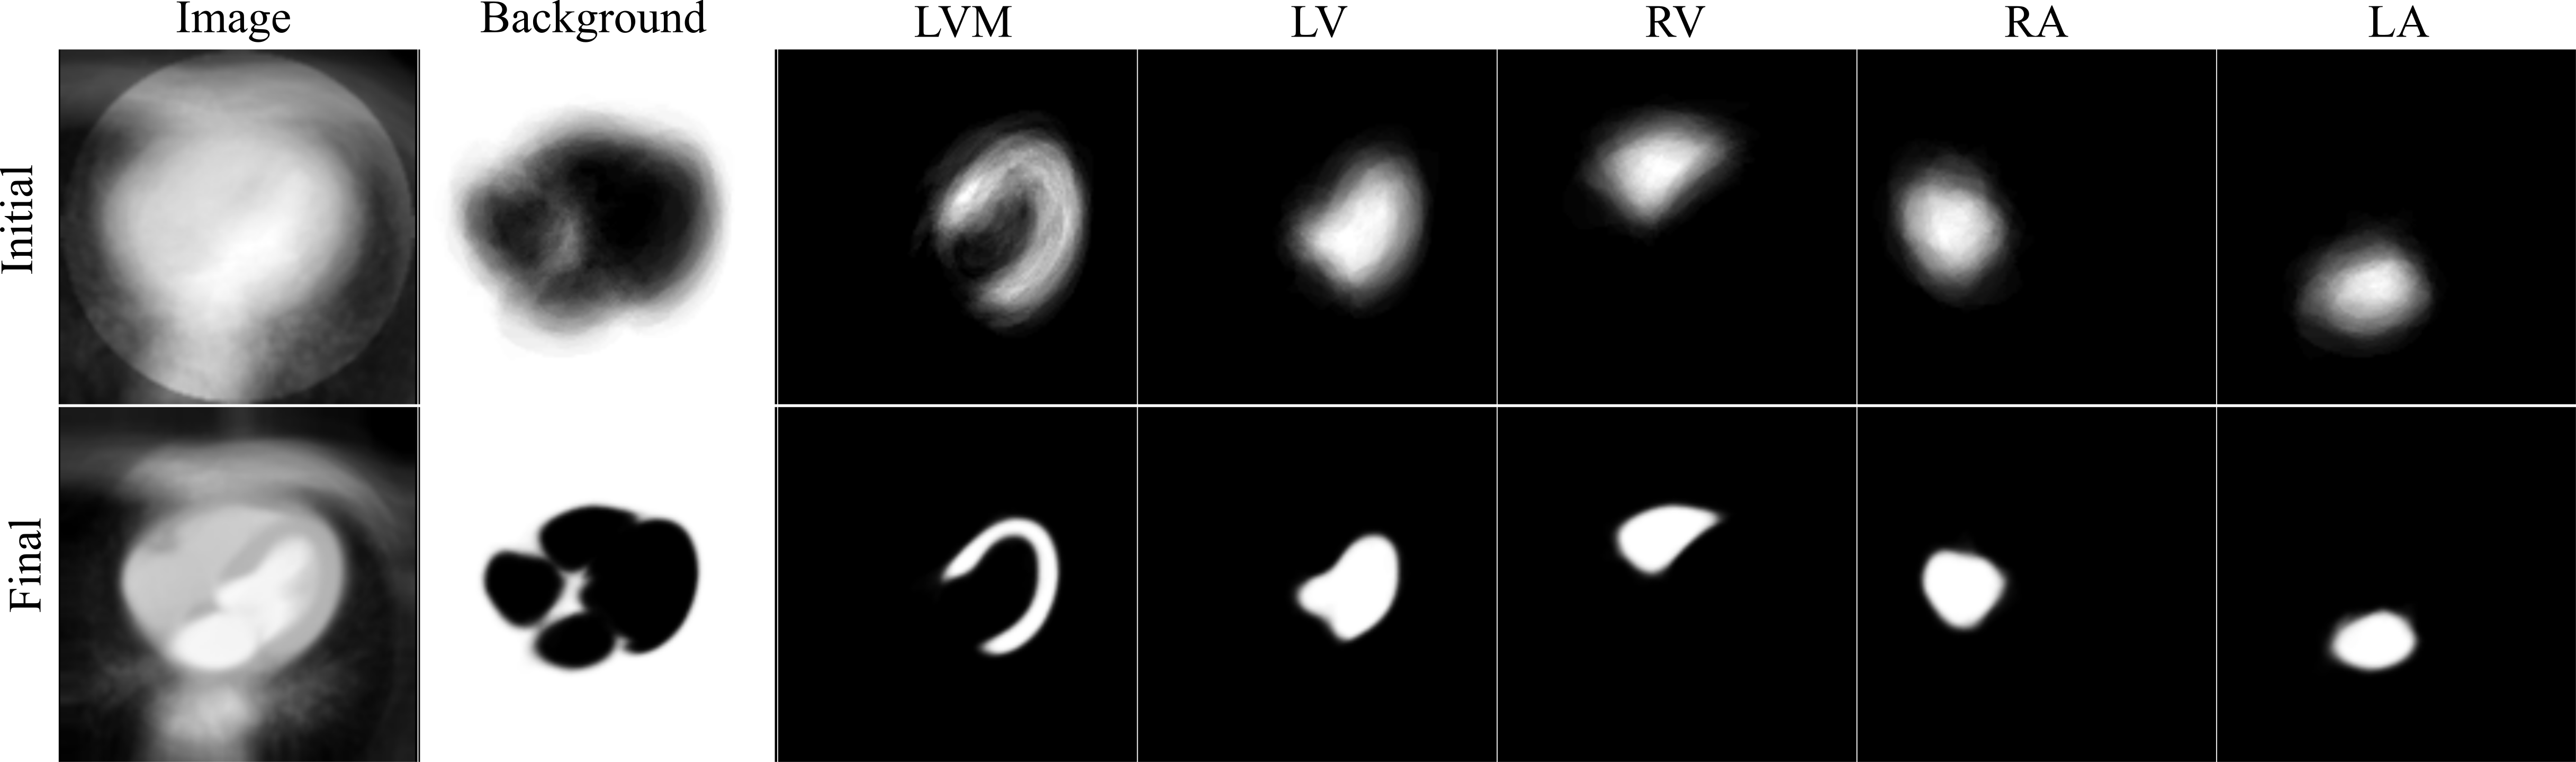

At the end of each training epoch, a forward pass through the network (Eq. (9)) is used to warp each training case to atlas space, from which the channel-wise mean atlas is computed (Eq. (16)). The updated atlas labelmap at the end of each epoch, () in Eq. (15), is then used during the following epoch in the computation of the losses (Eq. (11)) and (Eq. (12)). The atlas labelmap and image are shown in Fig. 2 alongside the labelmap and image of a randomly selected training case from the CCTA dataset.

Figure 9 shows the initial and final atlas image and multi-channel labelmap resulting from training Atlas-ISTN. The SoI in the final atlas image and labelmap are noticeably sharper, while the background structures in the atlas image remain fairly homogeneous. This is to be expected given that we are optimizing for the segmentation and alignment of the structures depicted in the labelmap. The final atlas image and labelmap are also shown in 3D in Fig. 2.